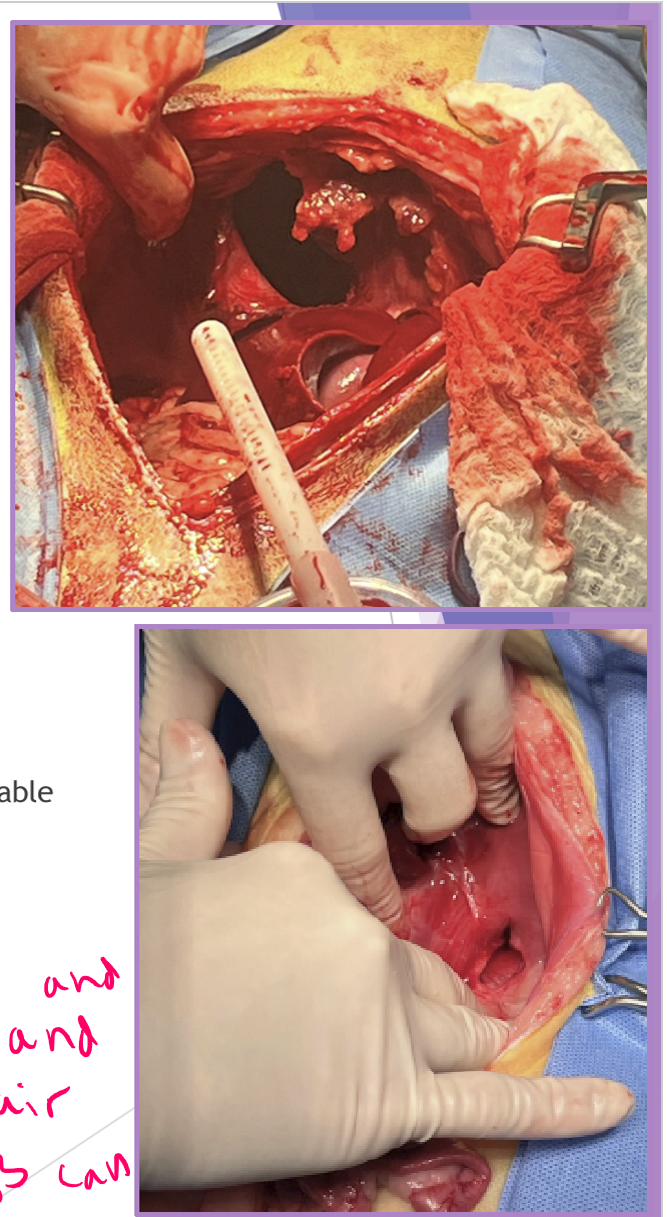

complete lobectomy - Torsion

surgery

complete lobectomy WITHOUT untwisting the lobe

Surgical repair - be prepared for anything!

abdominal exploratory

identify hernia and carefully reduce contents

caution - adhesions could be present

close diaphragmatic defect

account for tension

freshen edges if chronic

suture defect closed - simple continuous with absorbable suture

3-0 PDS

suture from dorsal (deep) to ventral (superficial)

remove air from thoracic cavity - with needle and syringe and pull air out so lungs can re-expand

do NOT re-expand lungs manually!!!

can cause re-expansion pulmonary edema